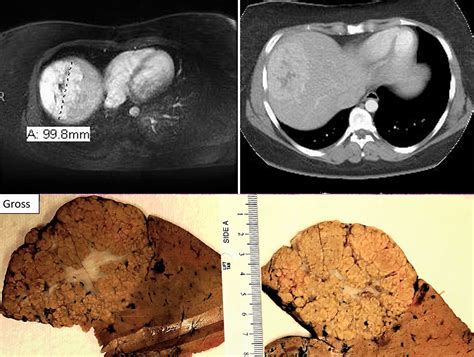

Focal Nodular Hyperplasia is the second most common benign liver tumor, right after the hepatic hemangioma. It is essentially a regenerative response of the liver to an underlying vascular malformation. Unlike malignant liver tumors, FNH does not represent a precursor to cancer, nor does it have the potential to spread to other parts of the body (metastasize). The lesion is composed of a disorganized, yet benign, arrangement of normal liver cells (hepatocytes), bile ducts, and blood vessels.

The hallmark of Focal Nodular Hyperplasia is the presence of a central fibrous scar. When radiologists view this mass through imaging technology, this central scar is a key diagnostic feature that helps distinguish it from other types of liver growths, such as hepatocellular adenomas or malignant carcinomas.

• MRI (Magnetic Resonance Imaging): This is the gold standard for diagnosing Focal Nodular Hyperplasia. Using specific contrast agents (like gadoxetate disodium), doctors can observe the unique way the mass absorbs and excretes the contrast, which is highly characteristic of FNH.

• CT Scan: Often shows a typical arterial enhancement pattern.